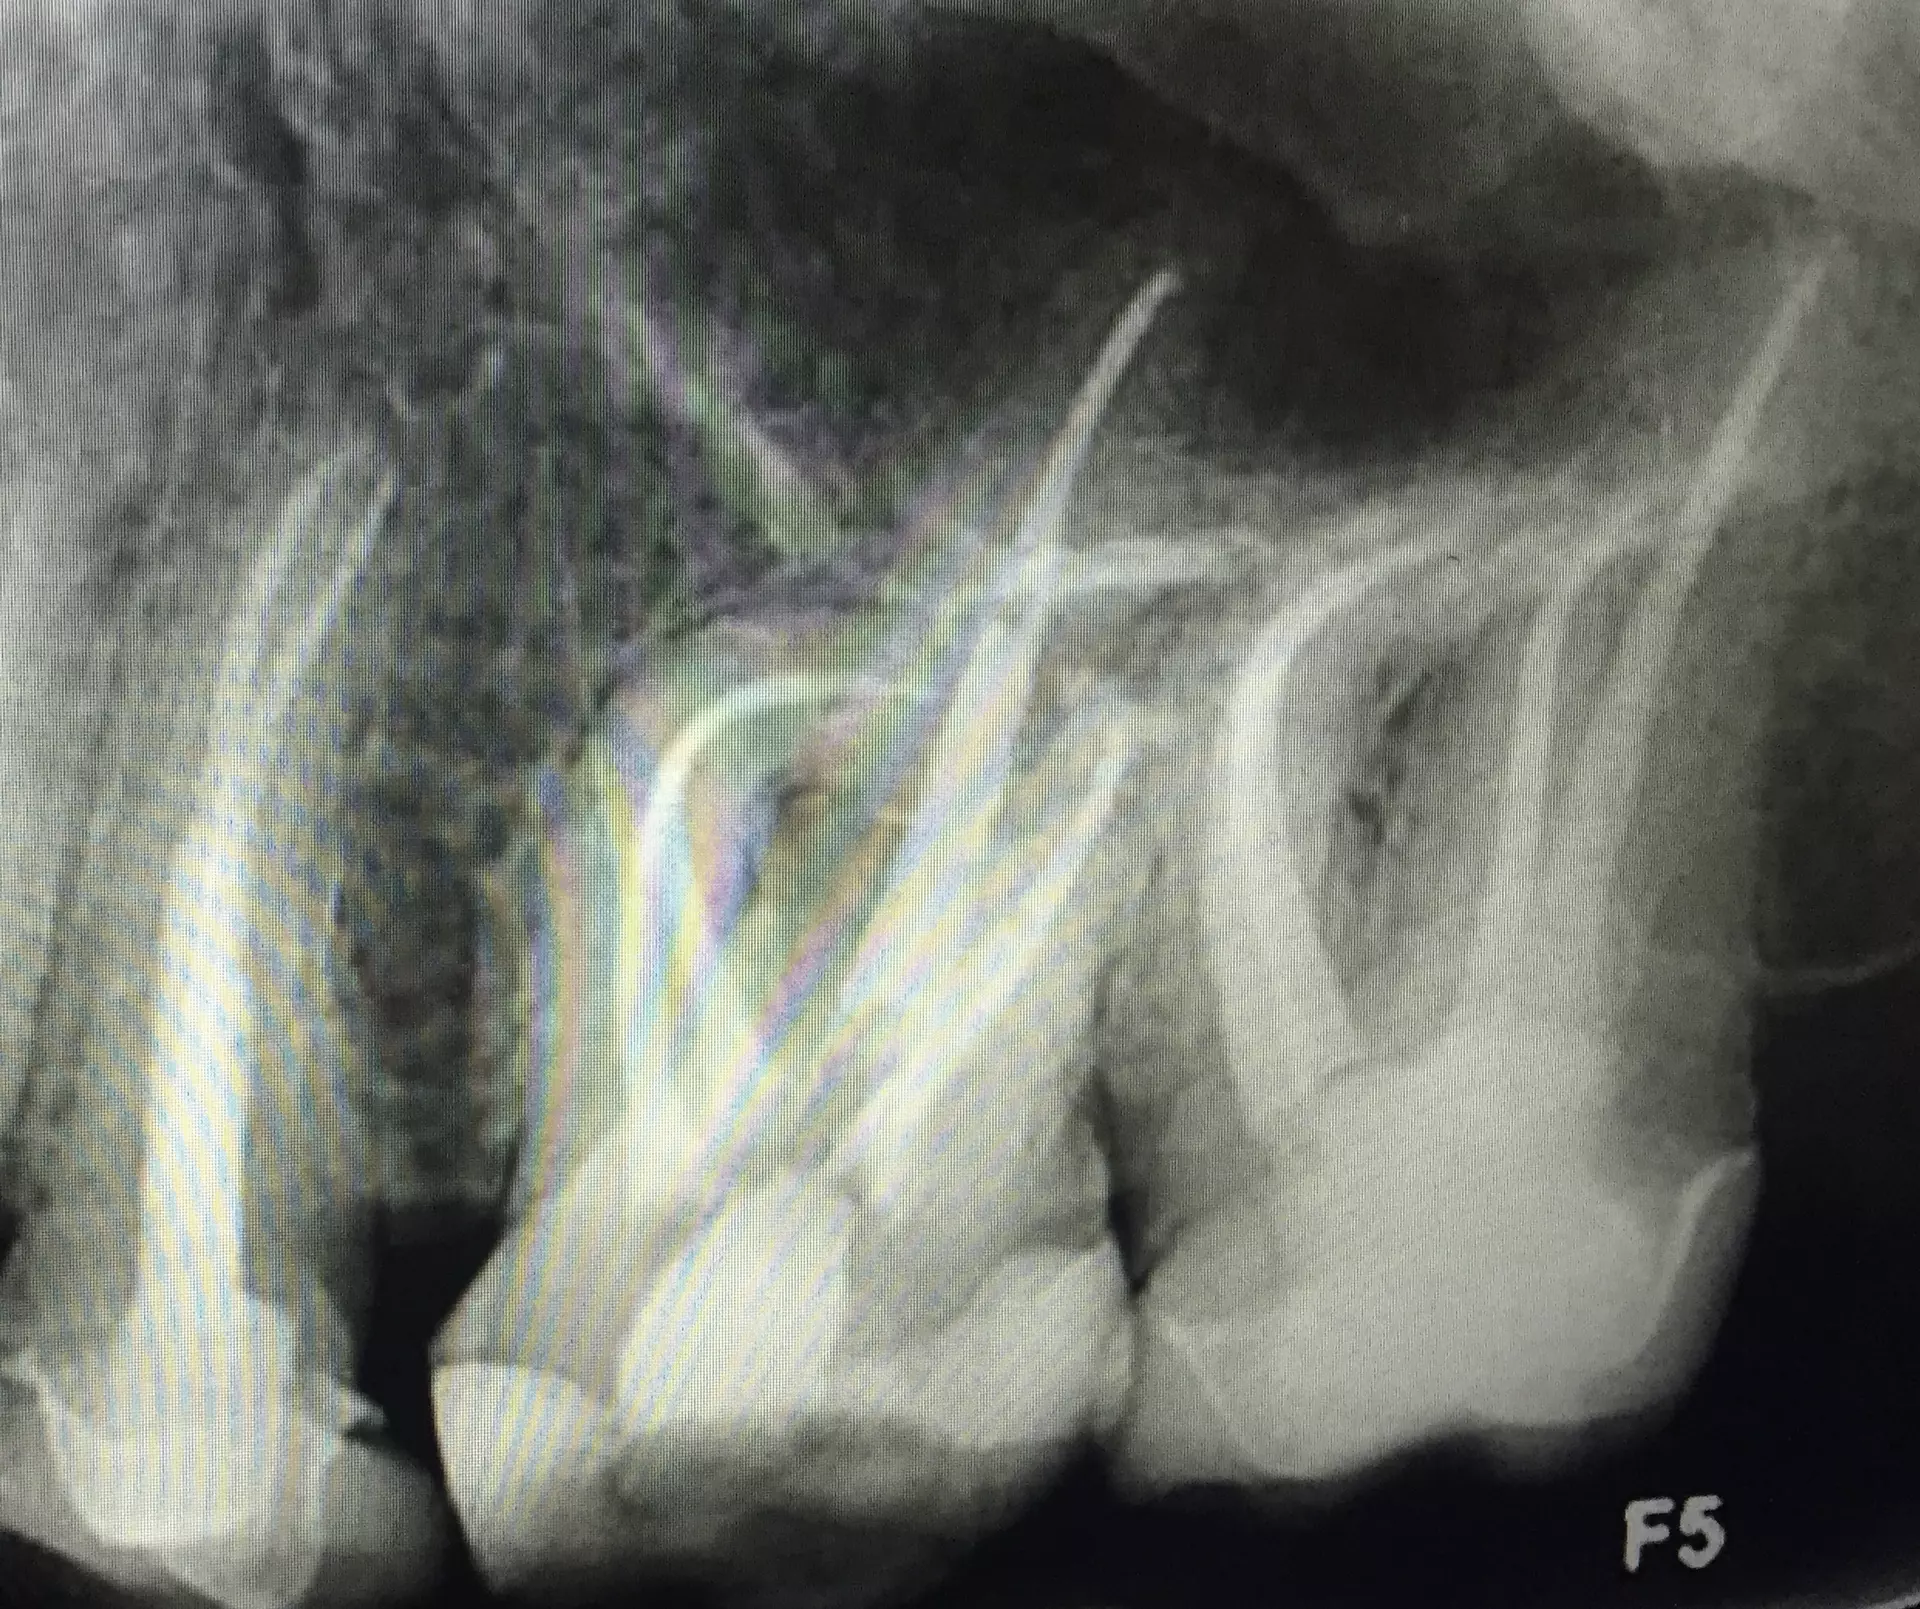

During root canal therapy, we will remove the infected pulp and thoroughly clean the root to then reshape the canal. To end the root canal, we will seal the tooth by using a biocompatible material and temporary filling. This procedure is typically done under local anesthesia to reduce any discomfort and pain the patient may experience during or after treatment. Root canals have an impressive 90% success rate with most procedures taking place in one session. Patients maintain the ability to drive home afterward and return to normal everyday activities shortly after their root canal. In some cases, we may place a crown on the treated tooth to better protect the root canal and ensure you regain full function and strength of your tooth.